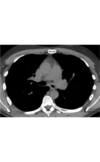

Coronal CECT of a patient with tracheobronchomegaly shows marked dilatation of the trachea (open arrow) and mainstem bronchi . The large airways have a corrugated appearance. Right lower lobe pneumonia (straight arrow) and paraseptal emphysema are also present.